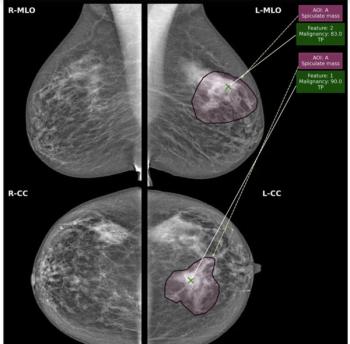

The AI software reportedly facilitates ease of use and improved accuracy in fetal ultrasound evaluations.